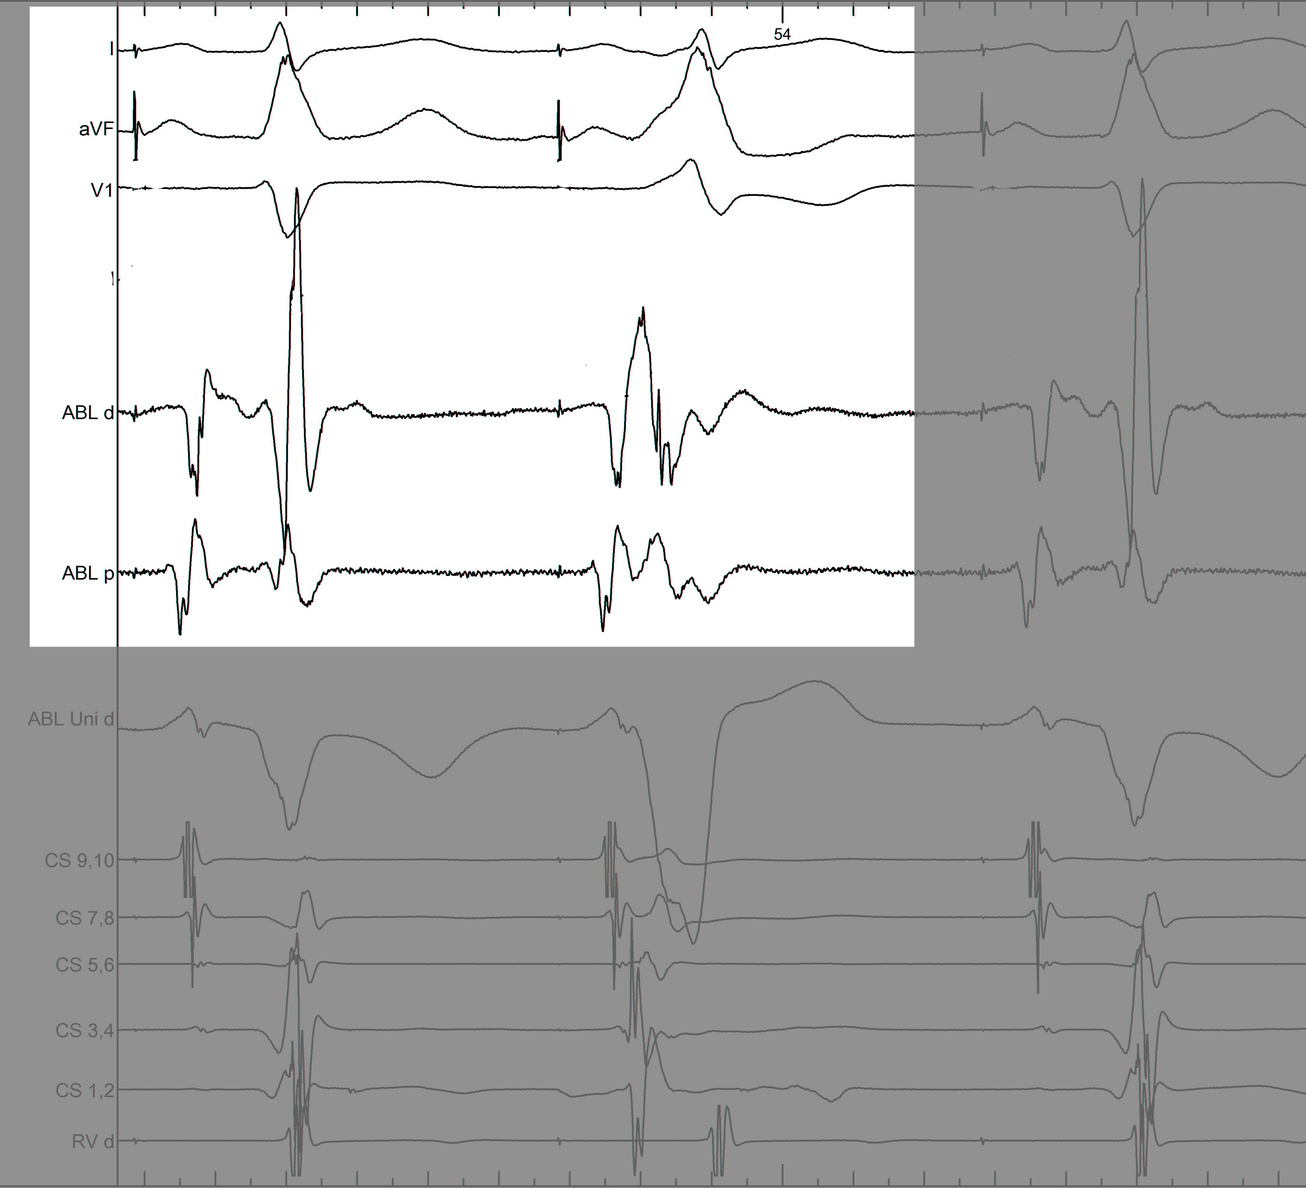

Identify components of the signal

mask1.jpg

mask2.jpg

mask3.jpg

mask4.jpg